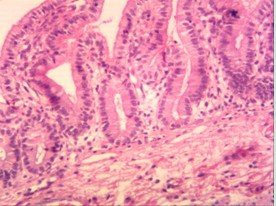

下面是實拍的圖片: